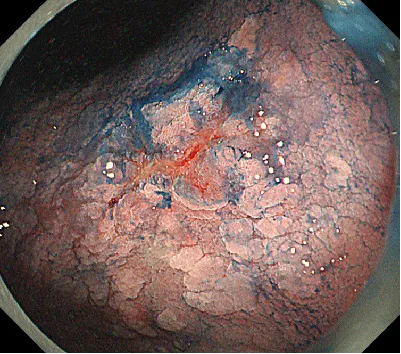

病例简介:林某,男,71岁,主诉:腹部隐痛不适8月余。胃镜胃角中央见一浅表隆起,中凹陷0-IIa+IIc)病变,大小约1.2cm×1.0cm,表面发红

11:23开始:左侧卧位操作。早癌病灶在2cm以内,萎缩背景,发红色调,ⅡC为主,分化型肿瘤可能性偏大,注意是否为混合性肿瘤,牵手型胃癌;这种病灶标记要标到肿瘤边界8-10mm左右,可以沿裂隙周边隆起做标记,把隆起部分都包进去活检一周内行ESD剥离影响不大2周后再行ESD会有纤维化形成,剥离难度会加大